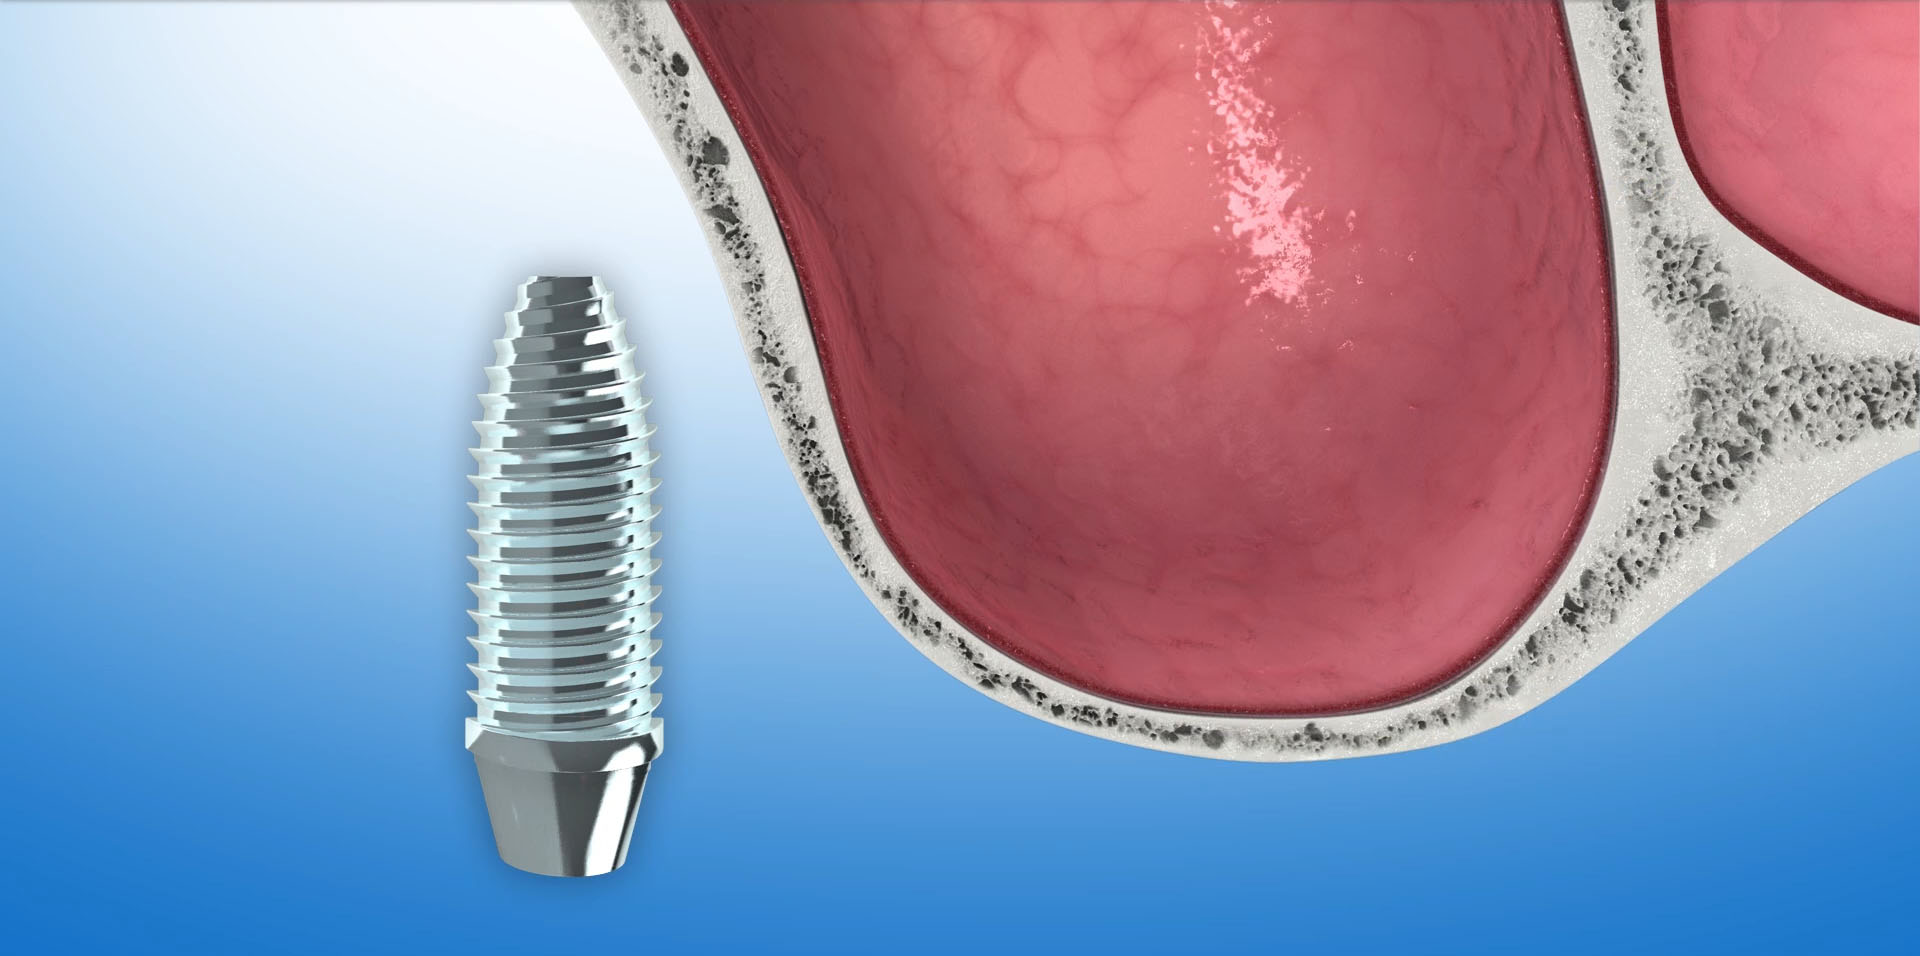

Za pomocą ultradźwięków, kość rozcinana jest wzdłuż szczytu wyrostka, na głębokość ok 1,5-2 cm. Następnie rozcięte blaszki kostne są rozchylane narzędziami ręcznymi. W przestrzeń pomiędzy rozchylone blaszki wyrostka wprowadzamy implanty, które utrzymują uzyskaną szerokość kości. Pozostałe wolne miejsca między rozszczepionymi blaszkami wyrostka uzupełniane są biomateriałem Bio-Oss. Cały obszar zabiegu pokrywany jest na koniec resorbowalna membraną Bio-Gide i zaszywany.

Nacisk rozchylonych blaszek kostnych na implant pozytywnie wpływa na jego stabilizację i przyczynia się do lepszego kontaktu kości z powierzchnią implantu.

Rozszczepienie wyrostka następuje za pomocą ultradźwięków – urządzeniem Surgysonic. Zostaje wprowadzony implant a szczeliny powstałe po rozszczepieniu wyrostka uzupełniane są biomateriałem Bio-Oss.